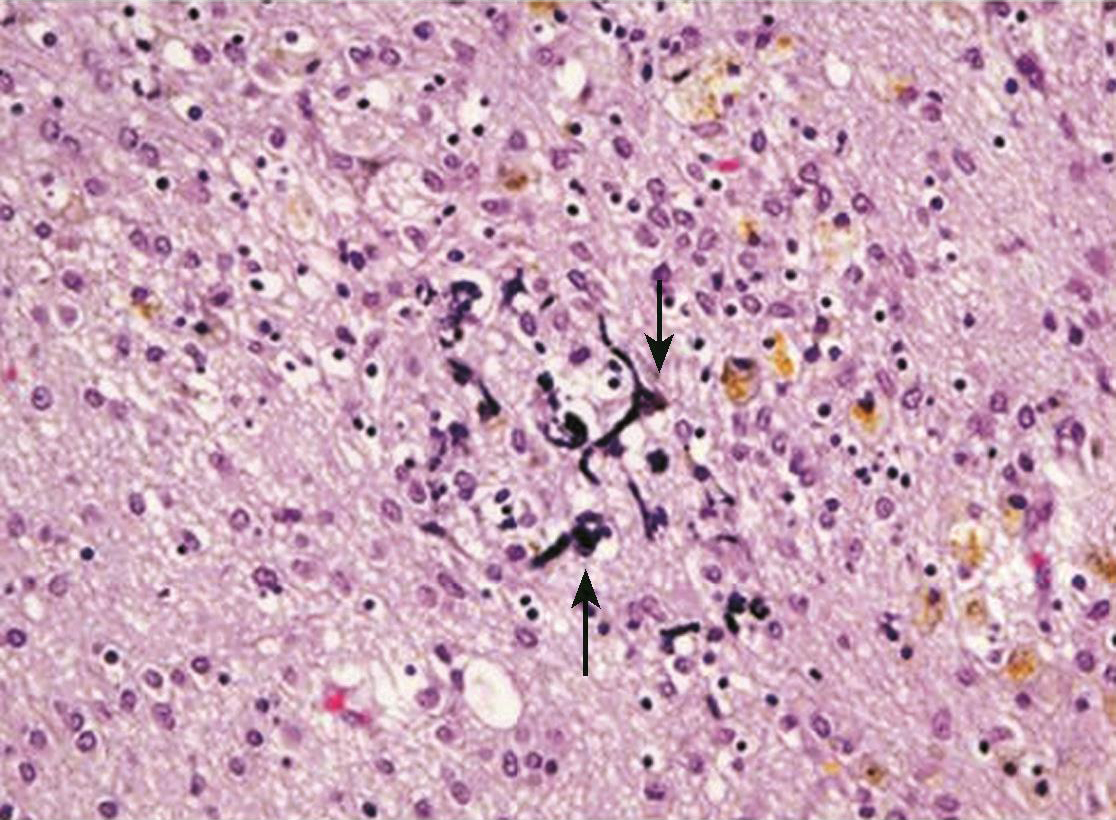

头部在受到急速作用力时,而引起脑相对运动,剪应力损伤可局限也可弥漫,表现为弥散轴索断裂、点片状出血和水肿(图2-4-6)。

图2-4-6 弥漫性轴索损伤病理表现

损伤位置病理变化如黑色箭头所示